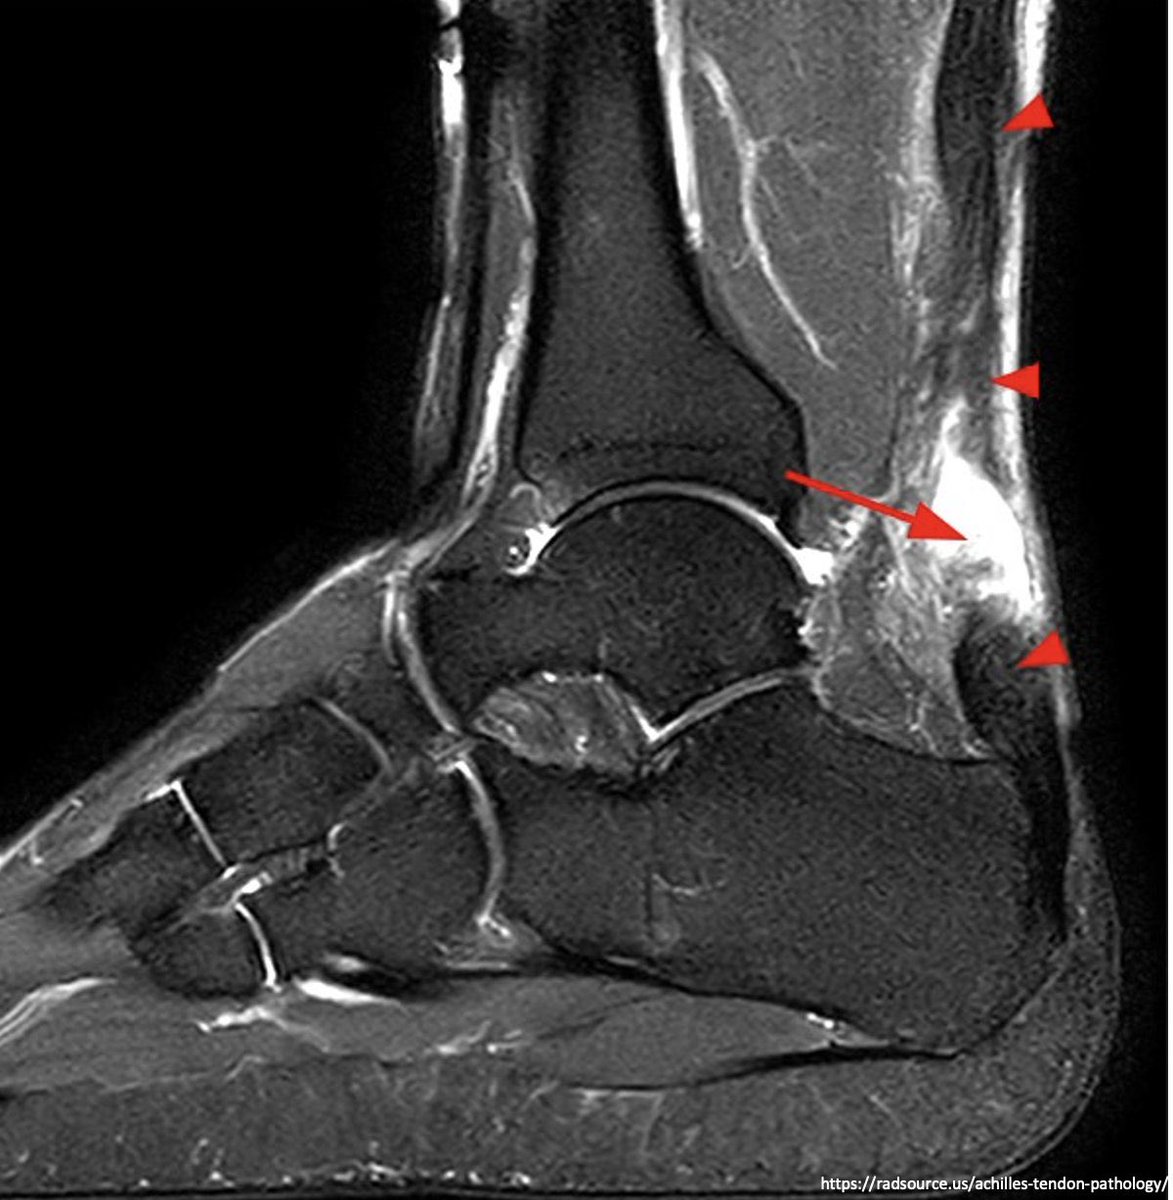

A middle aged patient presented with acute onset of ankle pain while playing squash. He takes ciprofloxacin daily for UTI prophylaxis. What is the likely diagnosis? #medtwitter